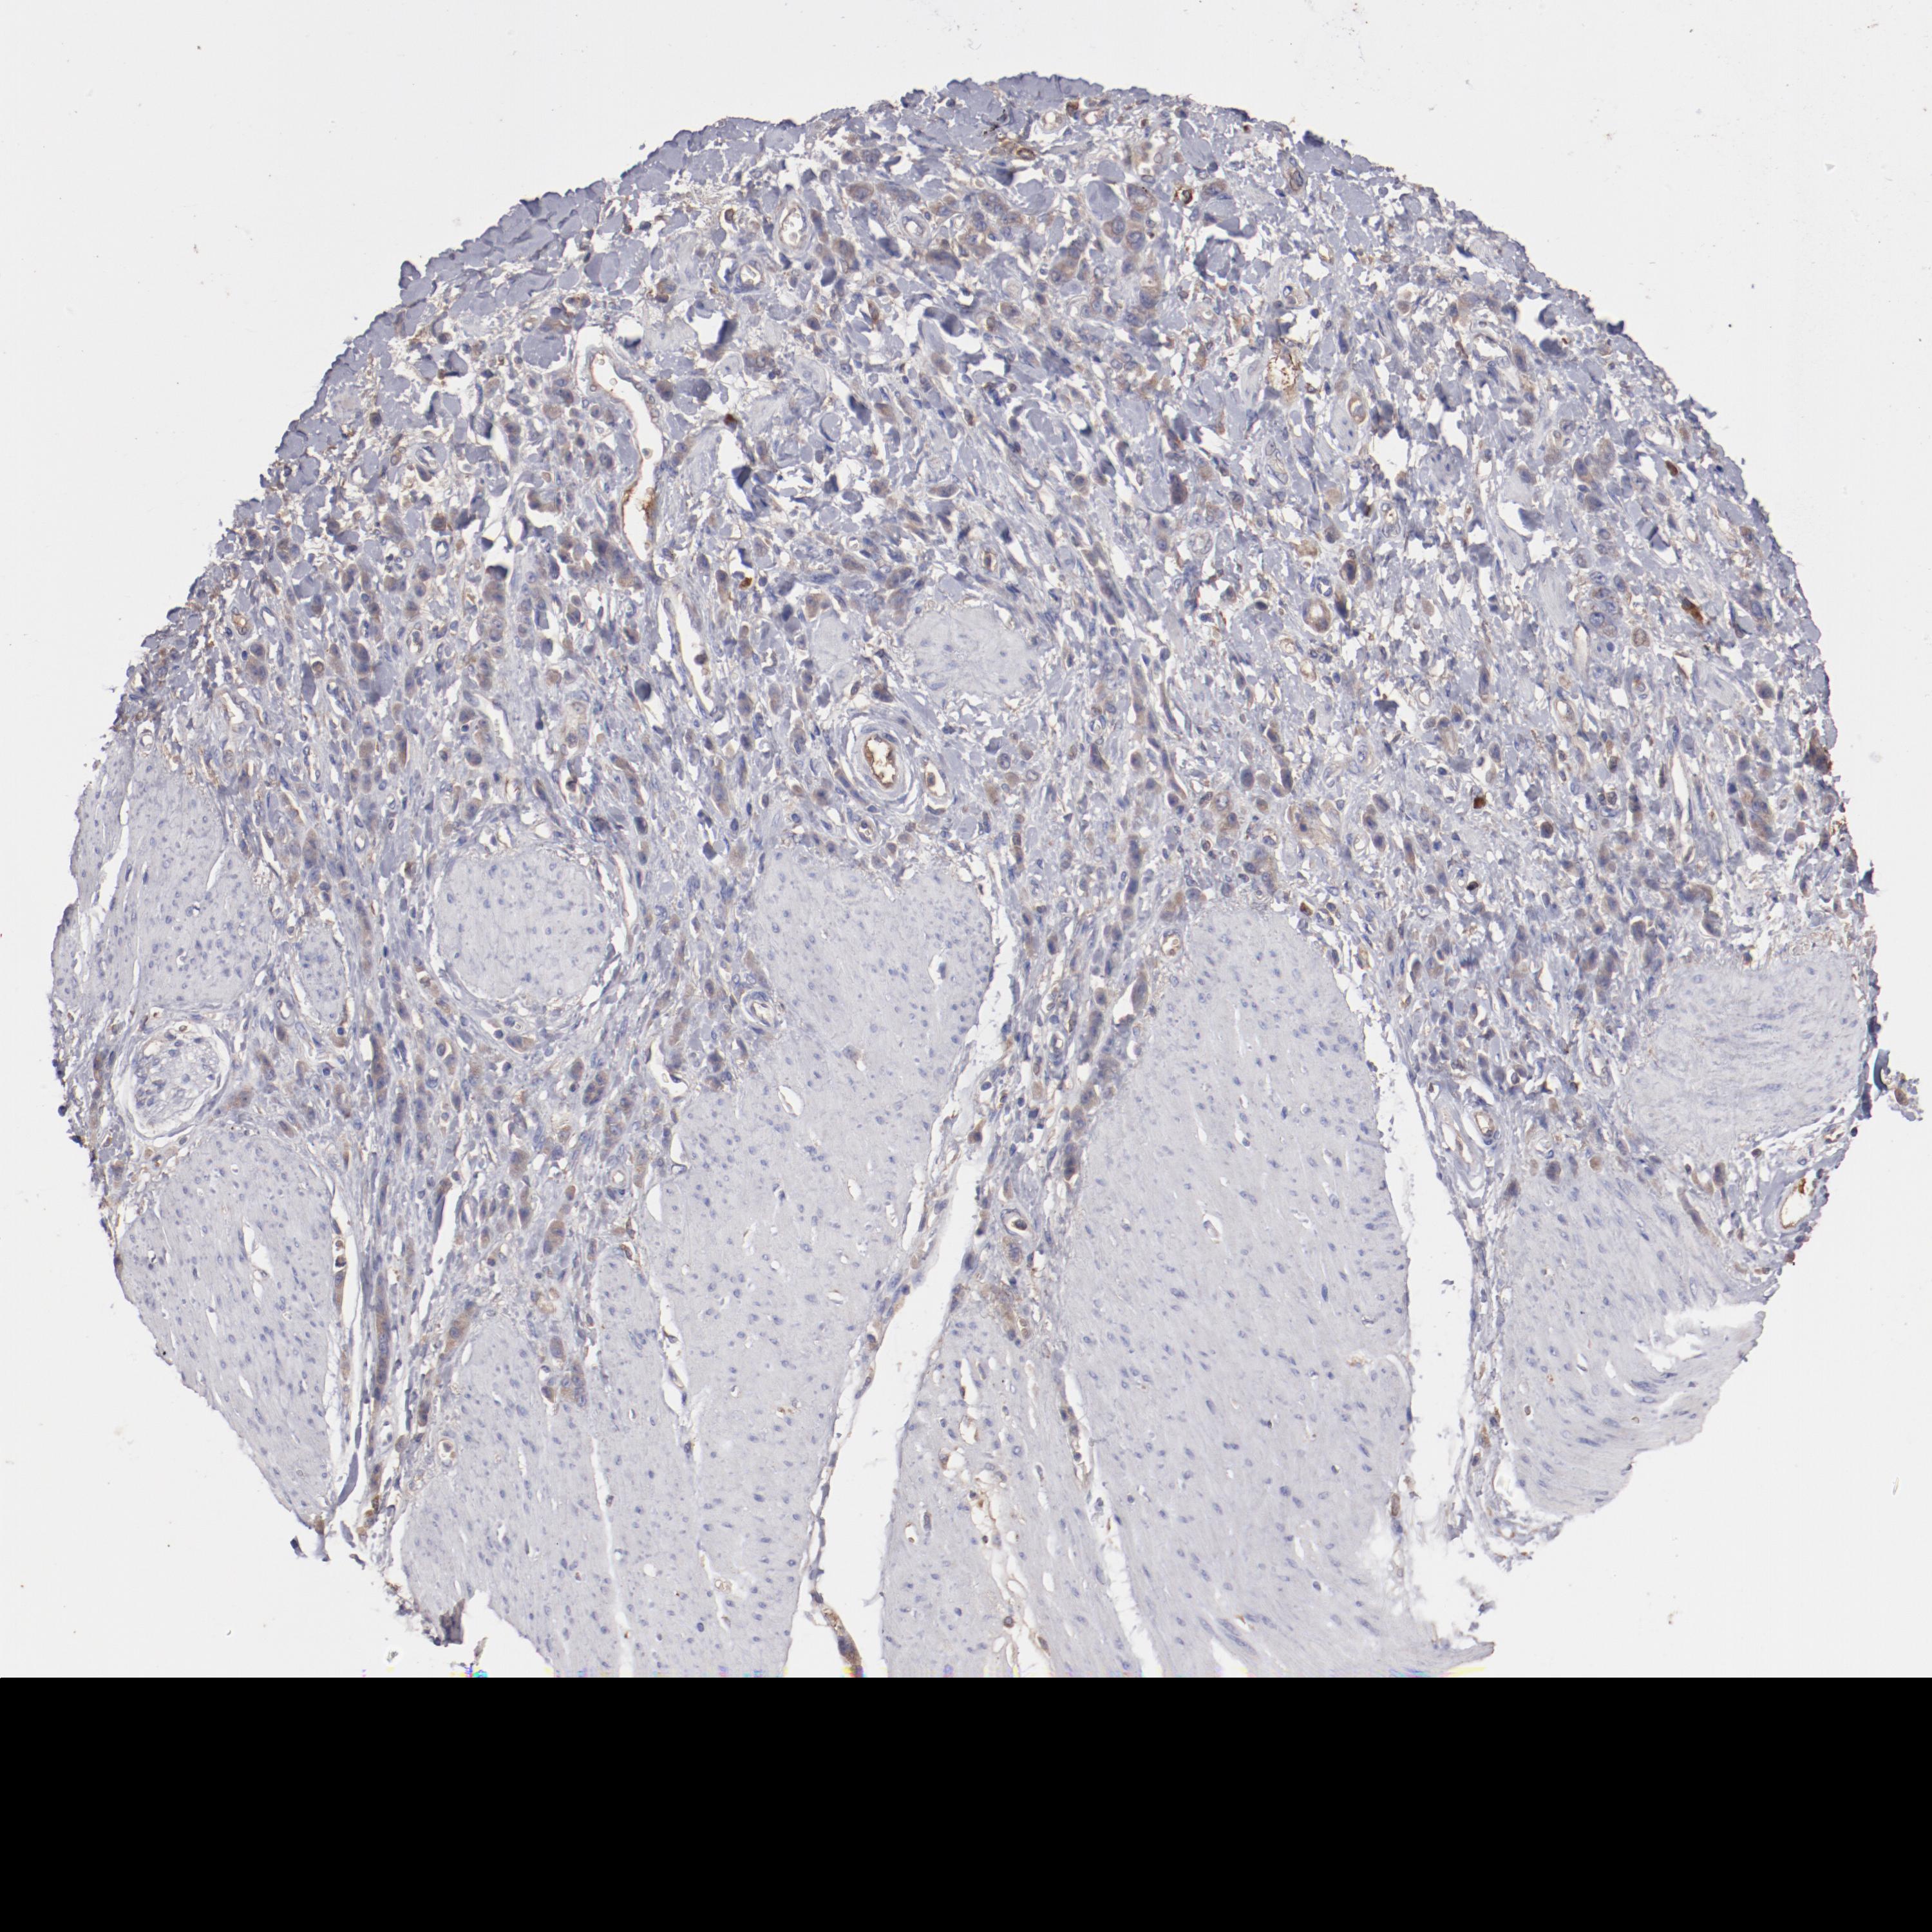

STOMACH CANCER - Protein expressioni

A mouse-over function shows sample information and annotation data. Click on an image to view it in a full screen mode. Samples can be filtered based on level of antibody staining by selecting one or several of the following categories: high, medium, low and not detected. The assay and annotation is described here.

Note that samples used for immunohistochemistry by the Human Protein Atlas do not correspond to samples in the TCGA dataset.

Antibody stainingi

Antibody staining in the annotated cell types in the current human tissue is reported as not detected, low, medium, or high, based on conventional immunohistochemistry profiling in selected tissues. This score is based on the combination of the staining intensity and fraction of stained cells.

Each image is clickable and will lead to virtual microscopy that enables deeper exploration of all samples and also displays staining intensity scores, fraction scores and subcellular localization as well as patient and tissue information for each sample.

Antibody HPA002692

Antibody HPA005941

Antibody CAB010272

Staining

High

Medium

Low

Not detected

Intensity

Strong

Moderate

Weak

Negative

Quantity

>75%

75%-25%

<25%

None

Location

Nuclear

Cytoplasmic/membranous

Cytoplasmic/membranous,nuclear

Adenocarcinoma, NOS

Adenocarcinoma, High grade